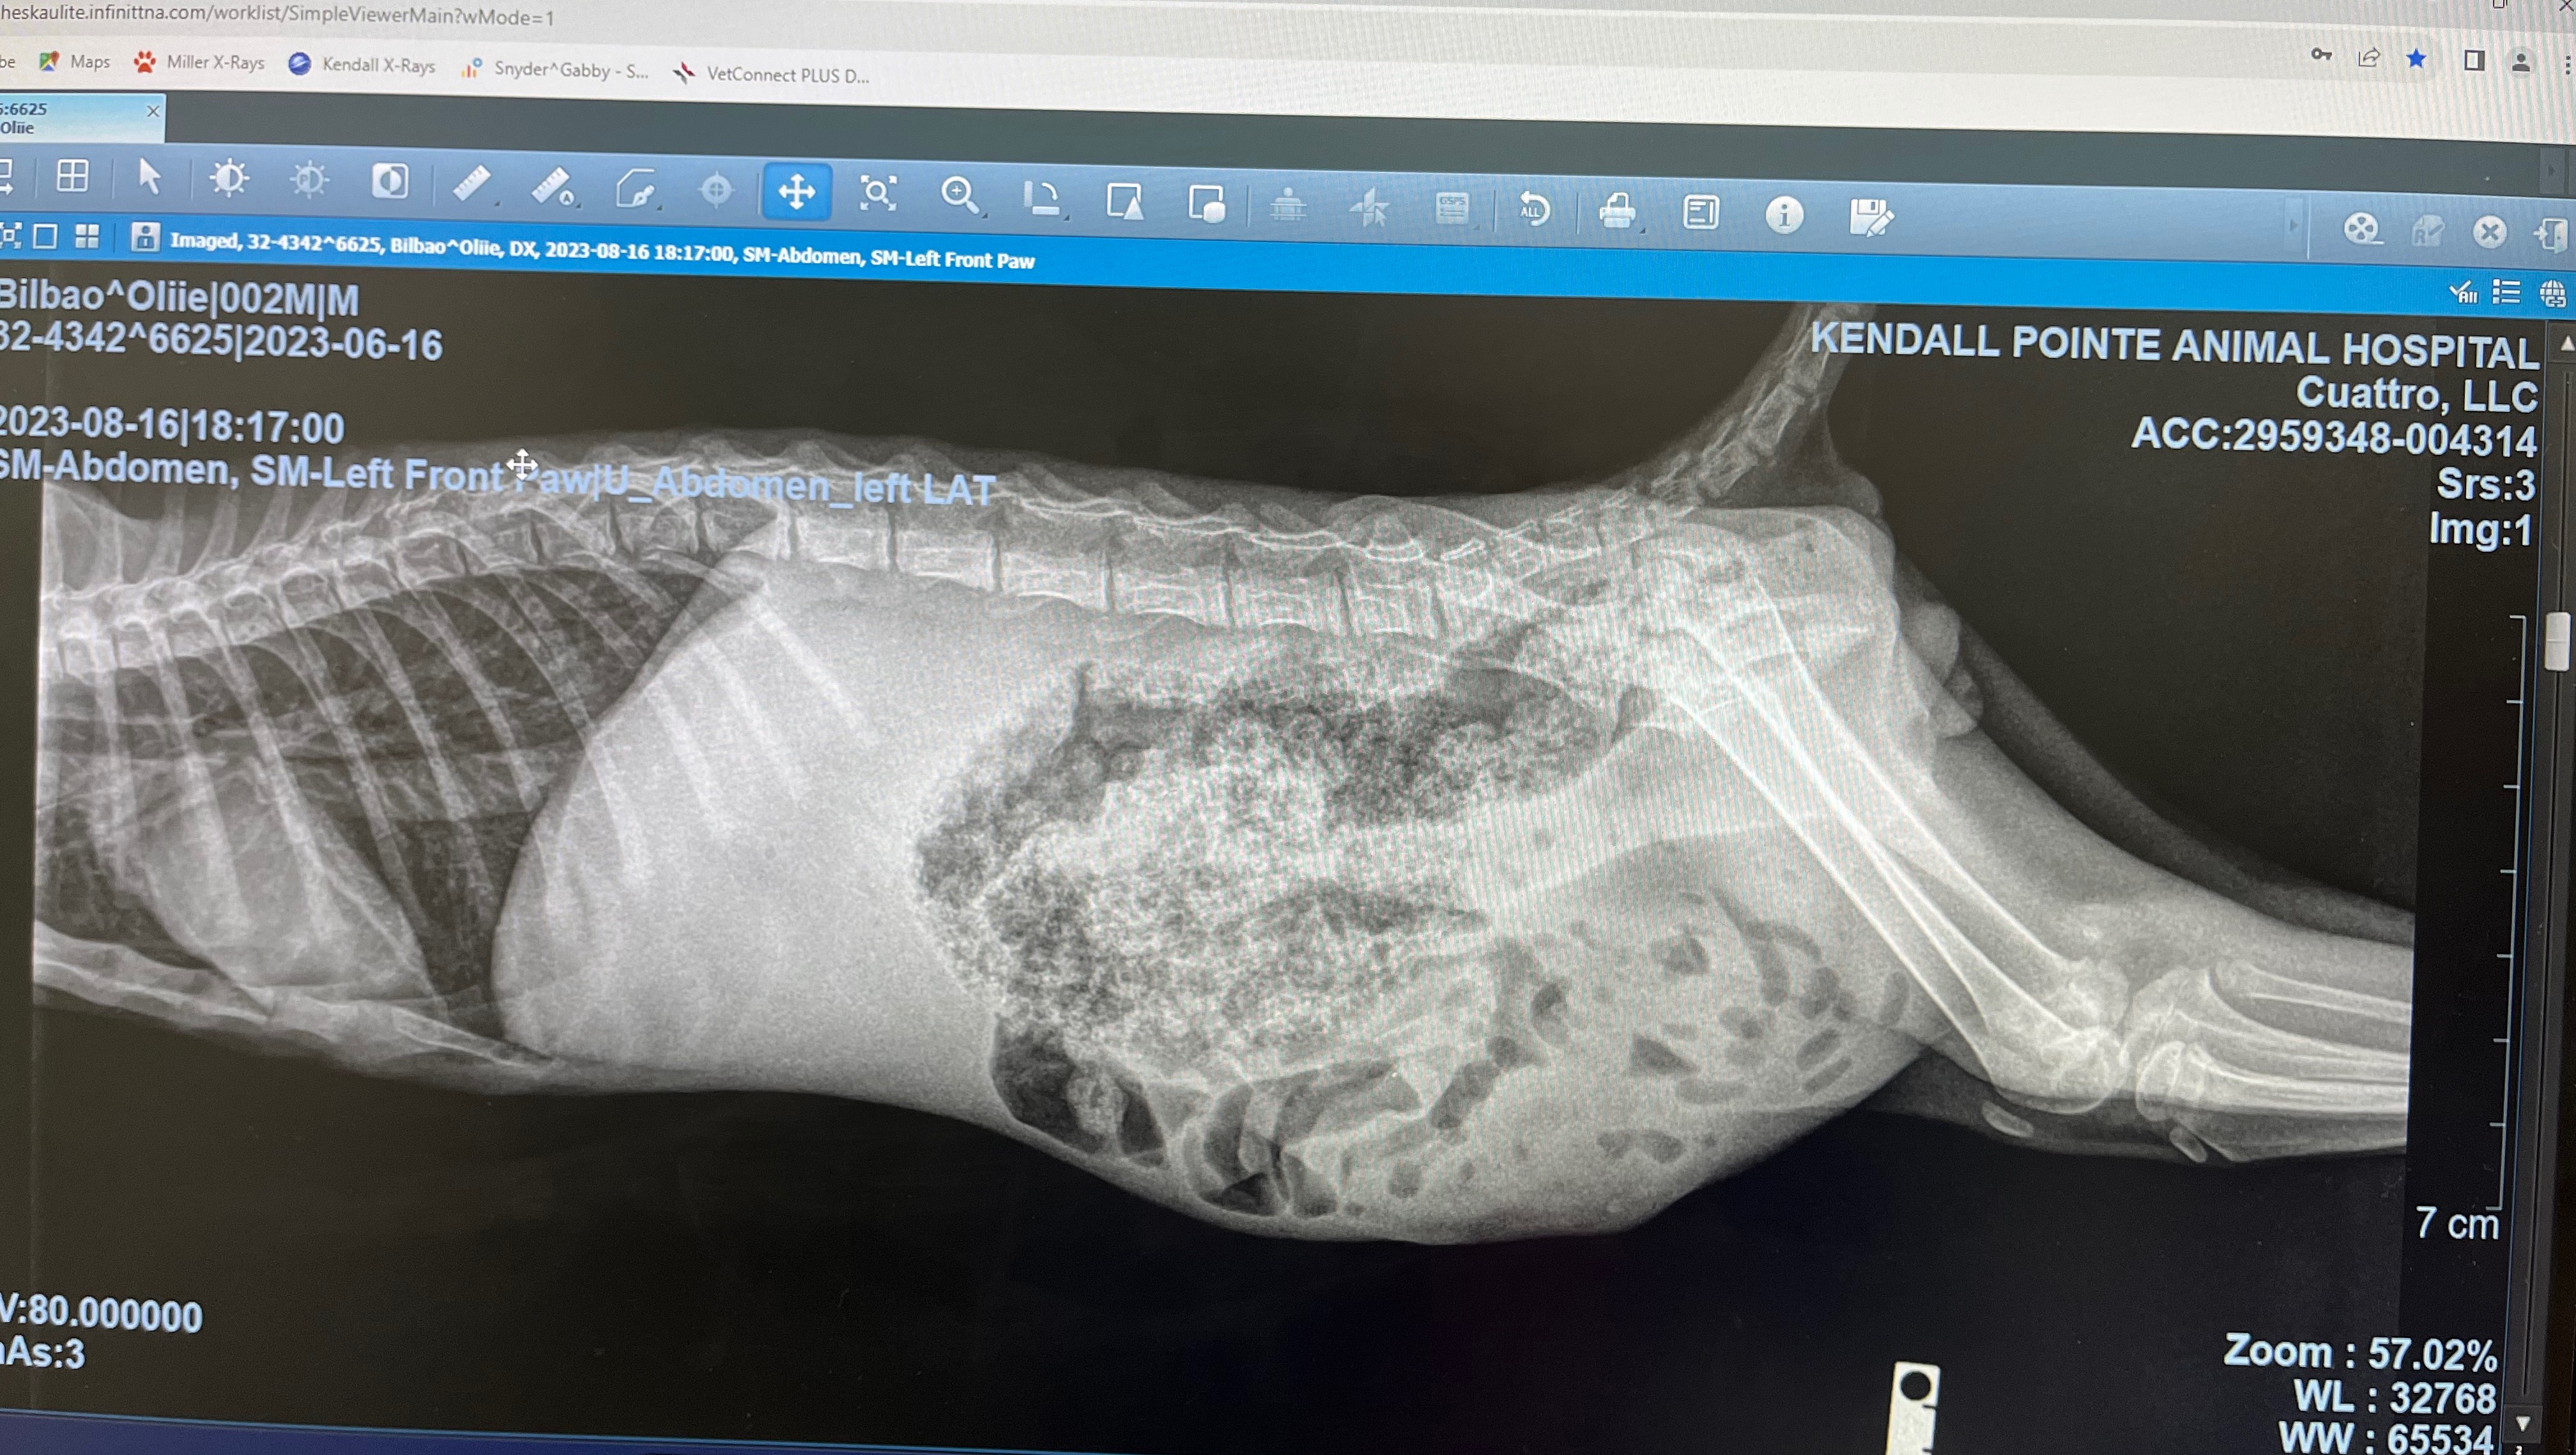

Hello, my name is Jocelyn I’m a foster for rescue cats/kittens in Miami. A few days ago I took in this 2 month old kitten, I named him Ollie. After seeing 3 vets it was determined that Ollie was hit by a car resulting in a broken front leg and abdominal hernia. Ollie is going to need 2 surgeries. Luckily I found a specialist that will perform both surgeries for $3,500. Ollie’s surgery is scheduled for Thursday August 24th. Ollie is a very strong and happy kitten who deserves a second chance. Please help me come up with the funds so Ollie can get his surgery, anything helps. Thank you so much. Below I have attached Ollie’s X-rays, vet bills so far & pictures of Ollie.